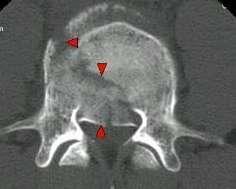

脊柱骨折:纵轴性暴力冲击,脊柱骤然过度前屈。X线表现为椎体压缩楔形变,前缘骨皮质嵌压,见横行不规则致密带,有时前方有分离的碎骨片,椎间隙正常,可合并脊椎后突成角;CT可充分显示脊椎骨折类型,骨碎片移位情况,椎管内骨碎片及狭窄情况。

X线平片:椎体压缩性骨折,可合并附件骨折

CT:观察骨折对脊髓和神经根的影响。 MRI:观察椎体骨折形态及信号(新鲜期T1低、T2高)、椎间盘 损伤、脊髓挫裂伤和受压、韧带撕裂

椎体爆裂骨折;单纯压缩骨折